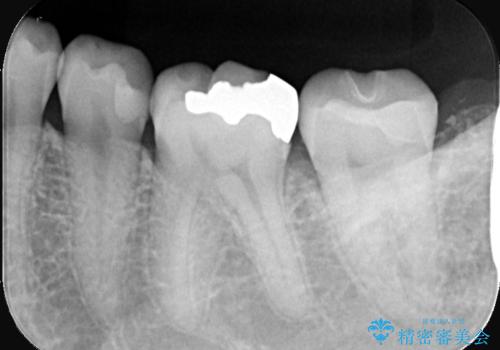

- 初診時にお口の中をチェックしたところ虫歯があり、大きさから部分的な詰め物のお話をしました。材料の特性を説明し、再び虫歯になりにくいセラミックインレーを選択されました。

セラミックインレー接着時にはラバーダム防湿を行いました。